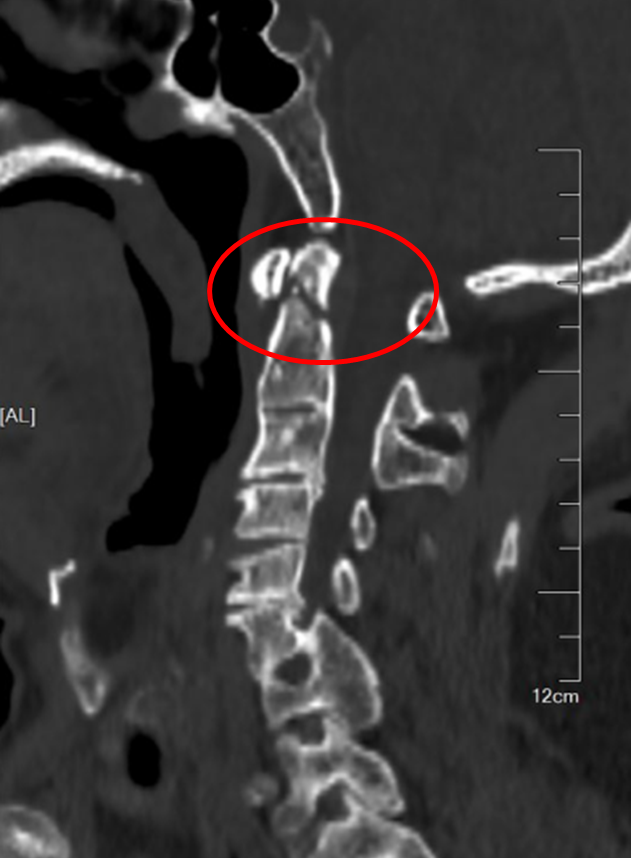

图3:骨科机器人

在麻醉手术科的严密监护下,刘义杰副主任医师首先熟练地完成了颈椎前路C3-4减压融合术(ACDF),成功解除了脊髓的压迫。然而,通过同一个仅3厘米的微小切口,精准地将螺钉植入游离且向后倾倒的齿状突具有极大的挑战性。关键时刻,骨科手术机器人发挥了“超级助手”的作用。团队利用机器人导航系统,对进钉点和角度进行了反复测算与调整,导针精准抵达目标。随后,由姜为民主任专利研发的一枚新型齿状突螺钉顺着通道顺利旋入,牢牢锁住了骨折端。整个过程出血量少,手术顺利完成。